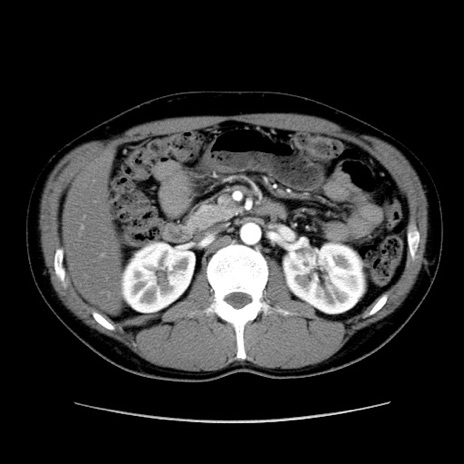

症例36(横断像)

【症例】20歳代 男性

【主訴】心窩部痛

【現病歴】今朝より上腹部痛あり。一旦軽快していたが再度出現したため救急要請。昨日夕に白身の魚を含む刺身を食べた。

【身体所見】BP 136/89mmHg、HR 74/min、BT 37.0℃、腹部:膨満、軟、心窩部に圧痛あり。反跳痛なし、筋性防御なし、腸雑音やや亢進あり。

【データ】WBC 17700、CRP 0.48